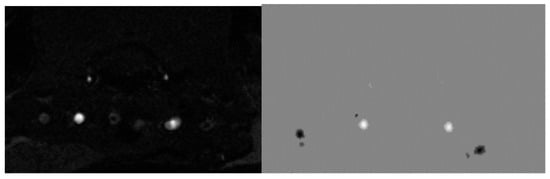

We performed the analysis of rat dorsal hippocampus neurometabolites following the execution of the abovementioned methods [57].

Voxels were manually placed according to a structural T2-weighted MRI image. All proton spectra were recorded by spatially localized single-voxel stimulated echo acquisition mode (STEAM) spectroscopy, with the following pulse sequence parameters: TE = 3 ms, TR = 5 s, and 120 accumulations. Uniformity of the magnetic field was tuned within the selected voxel using FastMap before each spectroscopic recording. The water signal was inhibited with a variable pulse power and optimized relaxation delays (VAPOR) sequence. The experimental 1H magnetic resonance spectra were processed, and the quantitative composition of metabolites was determined with a custom-made program similar to that of the LC Model software package [59,60]. The baseline correction was conducted automatically by the program to determine the spectral baseline for fitting the spectrum obtained by 1H MRS. The process of fitting was presented on the real-time plot, and the fitted data were stored in numerical form.

The facilities of the program allow the following 12 brain metabolites to be fitted to the MRS spectrum: N-acetylaspartate (NAA); phosphorylethanolamine (PEA); choline compounds (Cho); creatine + phosphocreatine (Cr + PCr); myo-inositol (mIno, Ins); alanine (Ala); lactate (Lac); glutamate + glutamine (Glu + Gln); aspartate (Ast); γ-aminobutyric acid (GABA); glycine (Gly); and taurine (Tau). The percentage ratios of metabolites were analyzed (Supplemental Table S1). Please see Figure 17 for corresponding images.

Figure 17. The regions of the MRS spectrum registration in three orthogonal planes of the brain of studied rats.